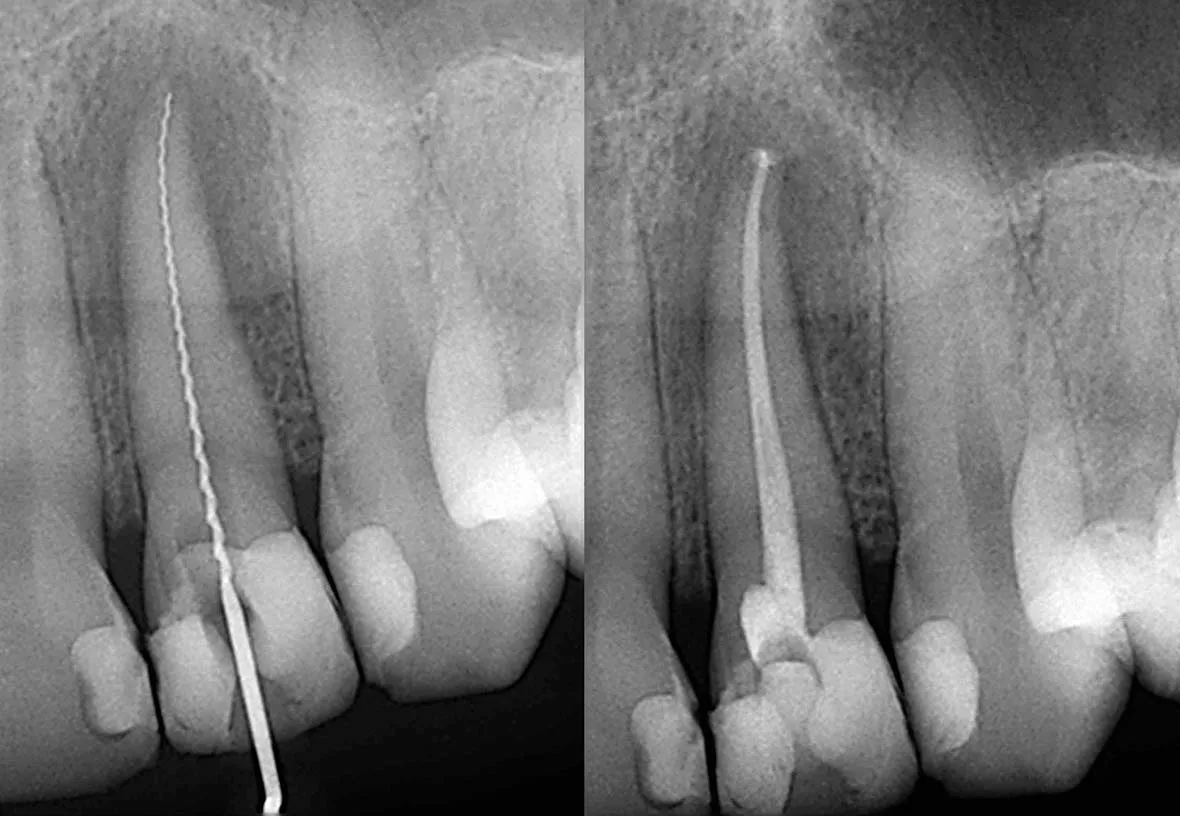

Root canal treatment involves the removal of the soft inner tissue of the tooth, also called the pulp. Your dentist will drill a tiny hole in the affected tooth and remove the pulp using special tools. After the pulp is removed, your dentist will clean the inside of the tooth to prevent further infection, fill the tooth with material, and seal the hole with a filling. After the procedure, your dentist will restore the tooth with a temporary dental crown while a permanent crown is being made.

root canal image